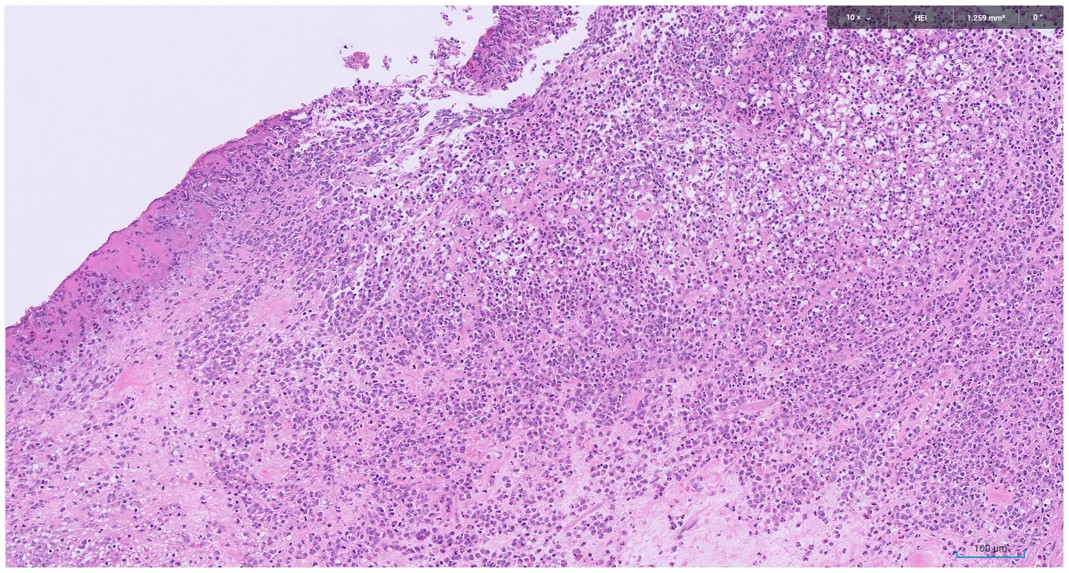

Microscopic image possibly detecting cancerous areas in human tissue

Radiation cystitis